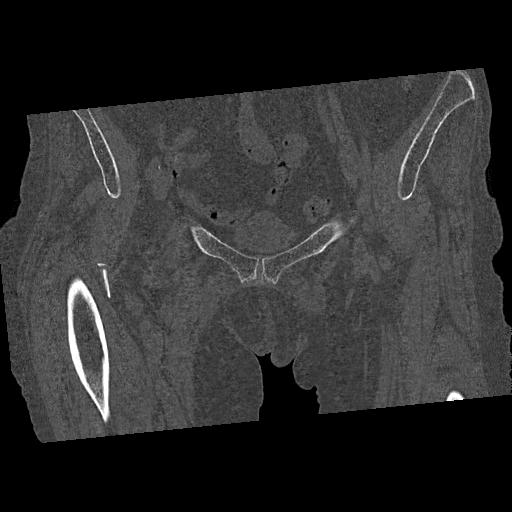

100703 1/27 両股正面+軸 1/29 両股正面+軸 94歳女性 パンソンロン